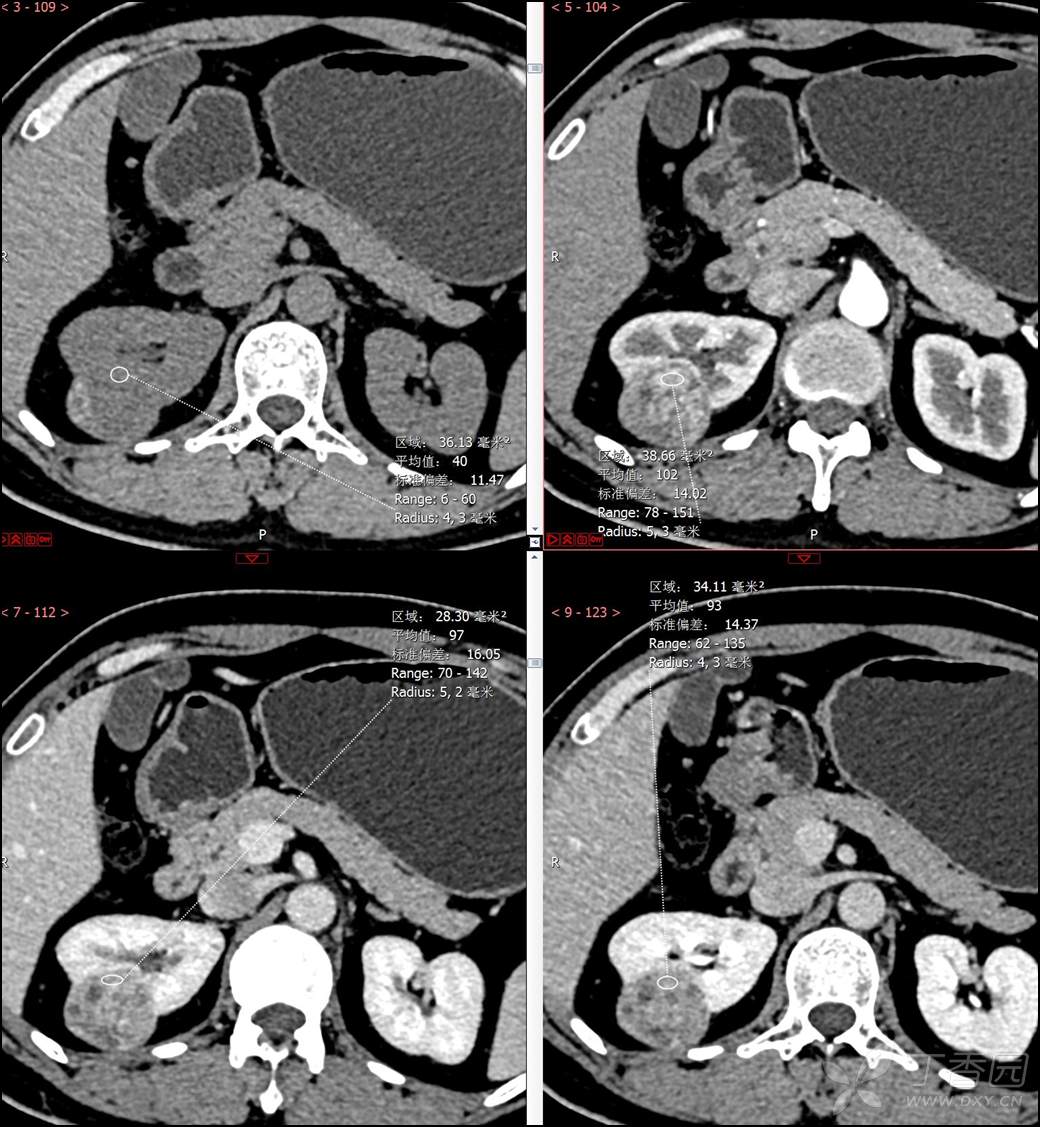

主诉:查体发现右肾肿物2月余

简要病史:患者2月余前于我院行健康查体,胸部(肺)CT平扫示:右肺中叶结节并右侧阻塞性肺炎;左肺上叶小结节;右肾占位。自诉无腰背部疼痛不适,无尿频、尿急、尿痛,无肉眼血尿,无恶心呕吐,无心悸、胸闷,无发热、寒战等不适,建议进一步检查。现患者为求进一步诊治于为我院就诊,建议手术治疗,门诊遂以“肾肿物(右)”收入院。患者自发病以来神志清,精神可,饮食可,睡眠欠佳,大便正常,体重近期无明显增减。